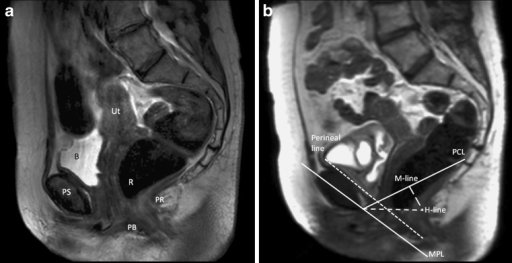

Understanding Cystocele and Rectocele: Causes, Symptoms, and Treatment Options Pelvic floor disorders such as cystocele…